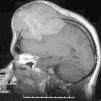

Leiomiosarcoma de cuero cabelludo.

Figuras (3)